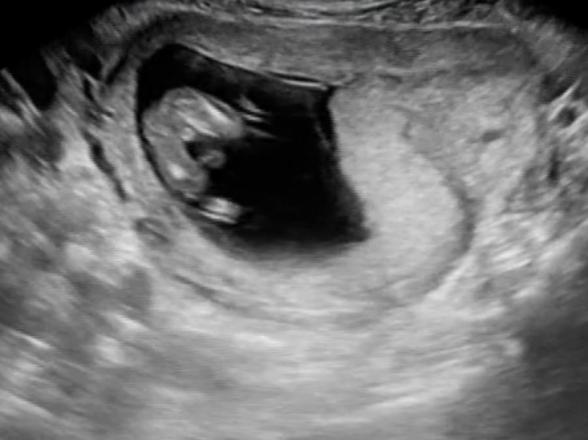

13週4日性別について

先日の検診にて股下からのエコーがあったので、性別についてお伺いしたいなと思いました😊

まだ早い時期なので正確なことは分からないと思いますが、よろしければご意見頂けると嬉しいです🙇♀️✨

エコーの写真拝見しました。

くっきりと写っている様ですが、写真だけでは判断が難しいです。

大変申し訳ありませんが、また次のエコー等でも確認いただけますと幸いです。